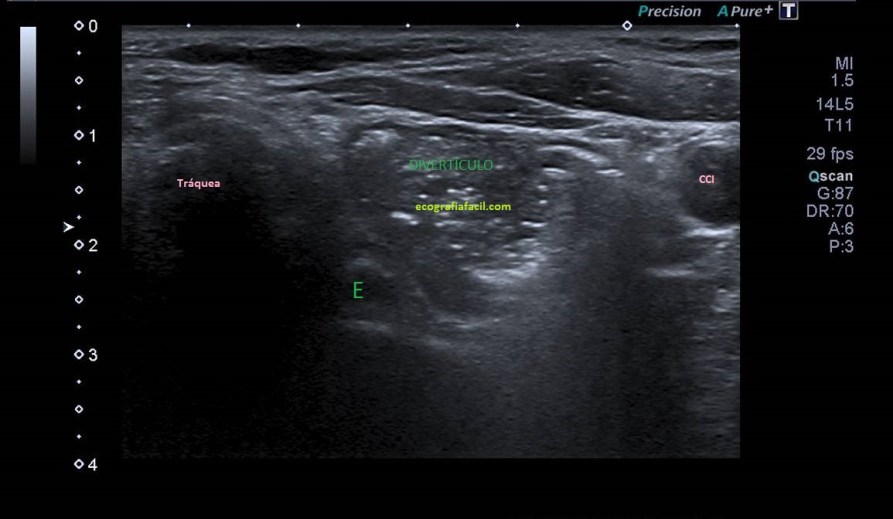

4

La sonda está en transversal al lóbulo tiroideo izquierdo. Se visualiza el esófago (E) y divertículo de Killiam-Jamieson.

Se visualiza divertículo esofágico (killiam- Jamieson) en longitudinal en la imagen 5.

Lo que observamos es un divertículo esofágico en la pared anterior y lateral del esófago cervical. Divertículo de Killiam-Jamieson.